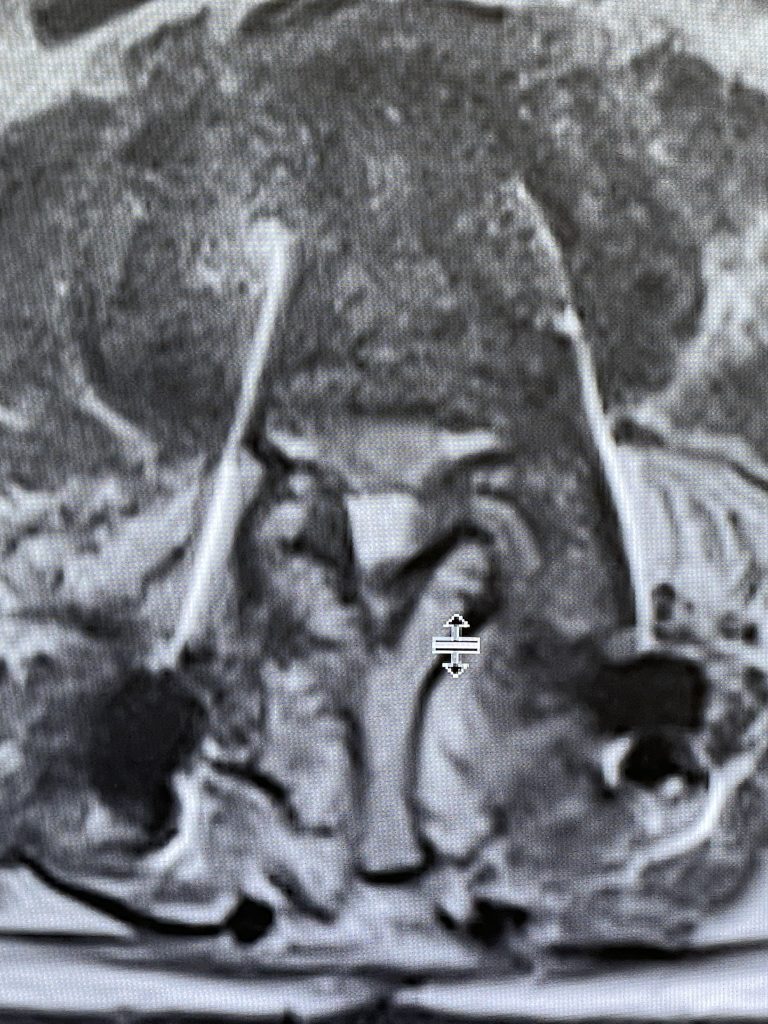

This 62-year-old female presents with chronic intractable low back pain with radiation down the front of her thighs. The patient had had two prior fusion surgeries: She initially had an L4-S1 fusion twelve years prior and a subsequent revision extension of her fusion at L3-4 that she had three years prior. She had a long-term history of smoking. She had mild hip flexor weakness, right greater than right. Imaging studies revealed next segment degeneration and stenosis at L2-3. (Figs. 1a and 1b and 2).

Figures 1a and 1b. Sagittal T2 MRIs of the lumbar spine demonstrating L2-3 stenosis after L3-4 instrumented fusion.